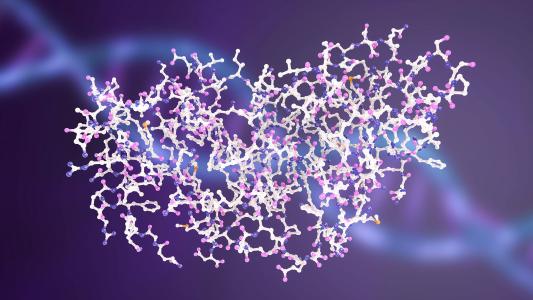

Researchers create blueprint for the “love hormone” receptor

The shape of the love hormone receptor is finally revealed in a 3D map created by researchers at the University of Zurich.